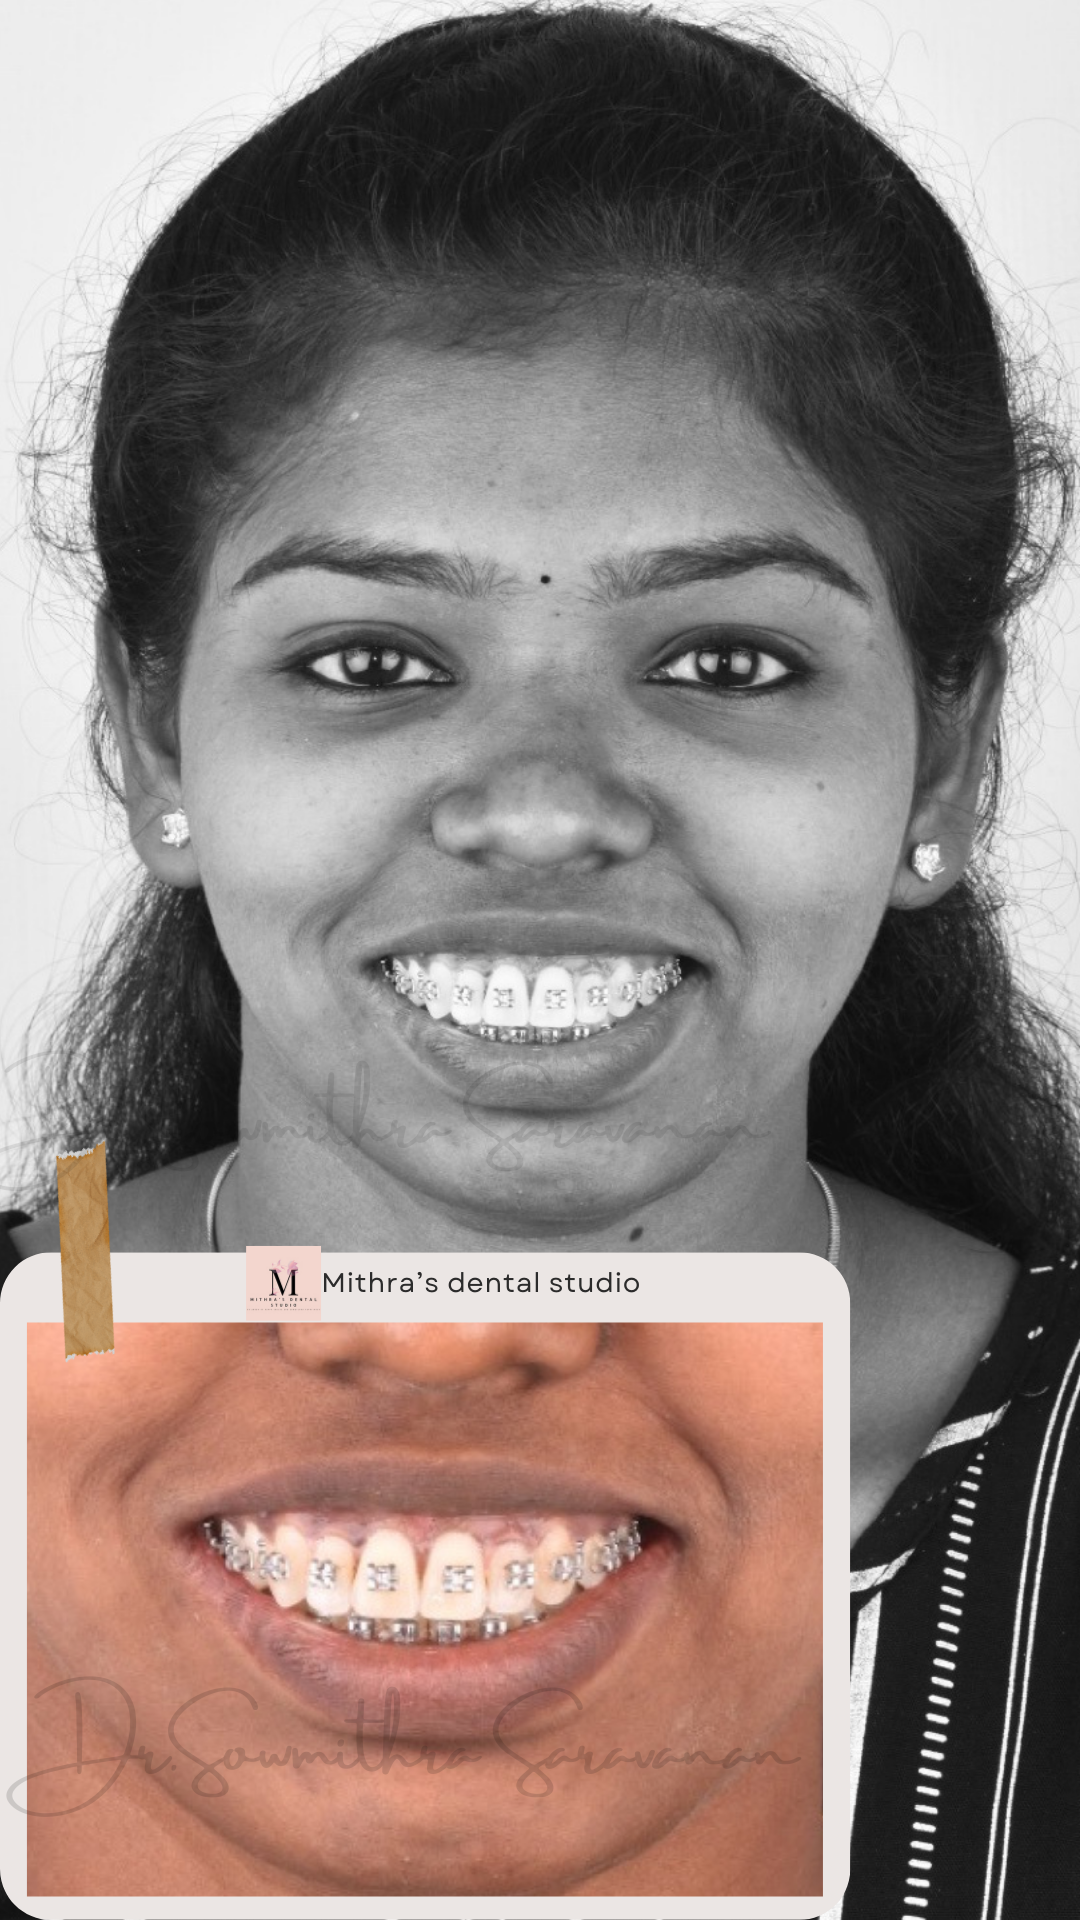

smile makeover

Smile Journey!

May be it is too simple to treat but the way this smile makeover made a difference in her life is immense! thats how wonderful smile curves are created!